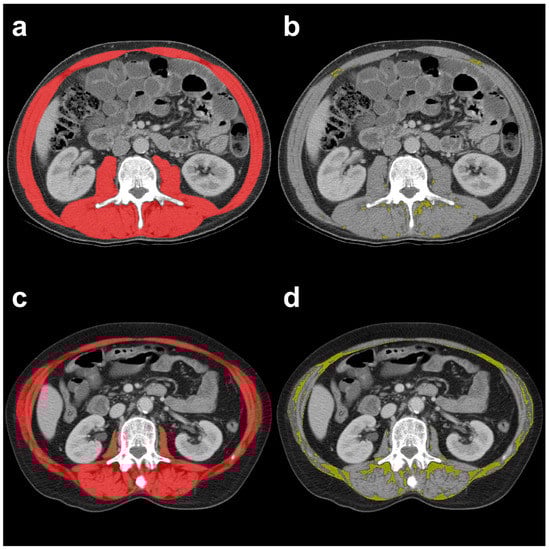

2.2. CT-Based Muscle Quantity and Quality